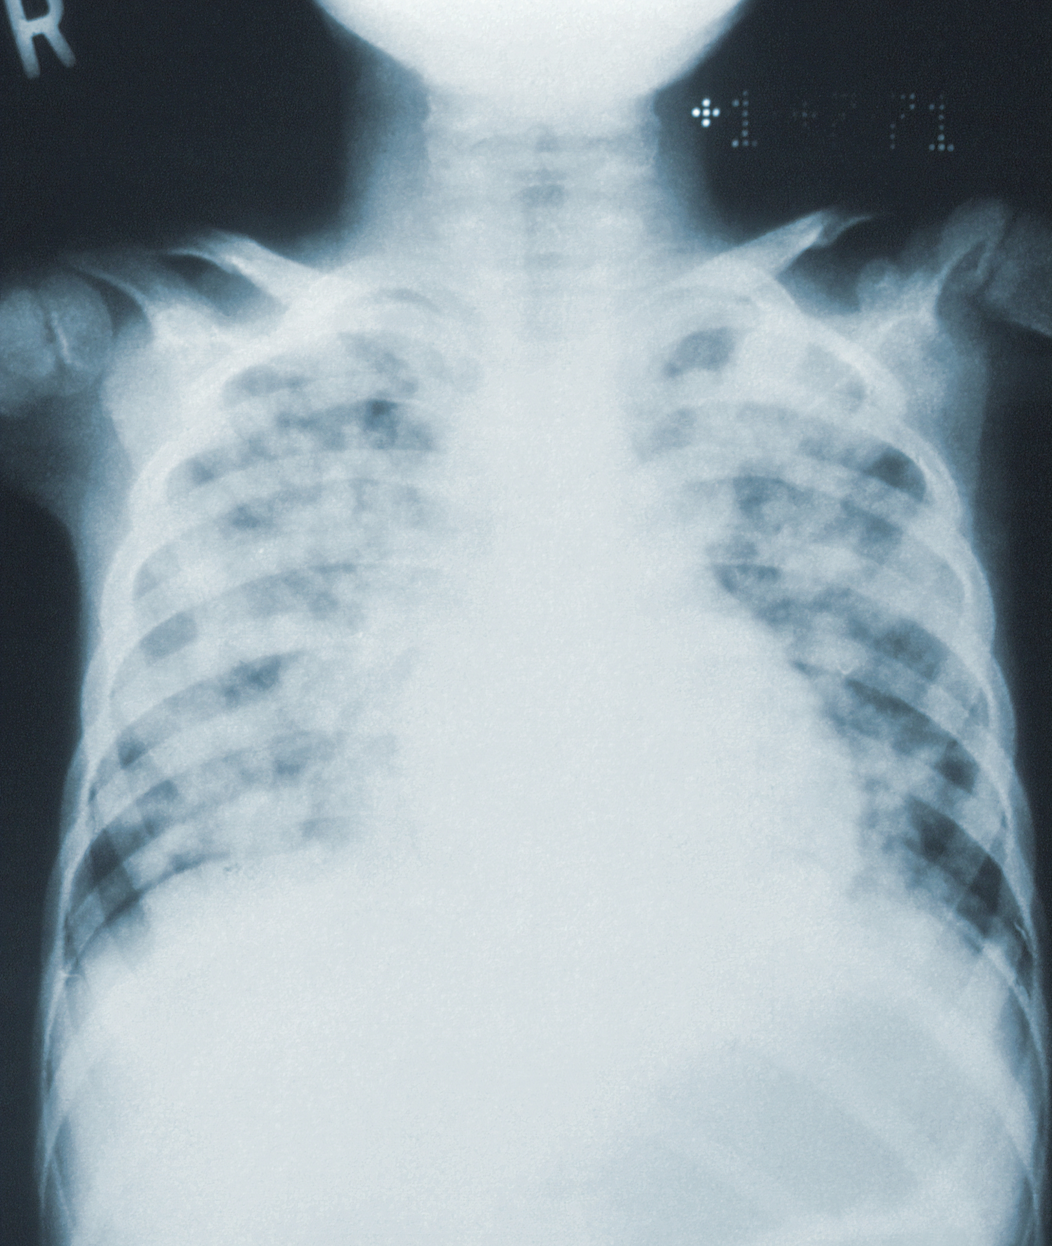

Mucus In Lungs X Ray Lungs Filled With Mucus After Covid Mucus, also known as phlegm when it’s produced by your respiratory system, lines the tissues of your body (such as your nose, mouth, throat, and lungs). You can get pneumonia as a. This is normal after respiratory infections. While most people recover from. As the swelling gets worse, your lungs fill with. It’s not surprising covid causes a cough, because. Lungs Filled With Mucus After Covid.

Mucus In Lungs X Ray Lungs Filled With Mucus After Covid As the swelling gets worse, your lungs fill with. You can get pneumonia as a. Mucus, also known as phlegm when it’s produced by your respiratory system, lines the tissues of your body (such as your nose, mouth, throat, and lungs). While most people recover from. It’s not surprising covid causes a cough, because the , from our nasal passages. Lungs Filled With Mucus After Covid.

Mucus In Lungs X Ray Lungs Filled With Mucus After Covid Coughing is one of the body’s ways of getting rid of unwanted irritants. Mucus, also known as phlegm when it’s produced by your respiratory system, lines the tissues of your body (such as your nose, mouth, throat, and lungs). Air sacs in the lungs fill with fluid, limiting their ability to take in oxygen and causing shortness of breath, cough. Lungs Filled With Mucus After Covid.